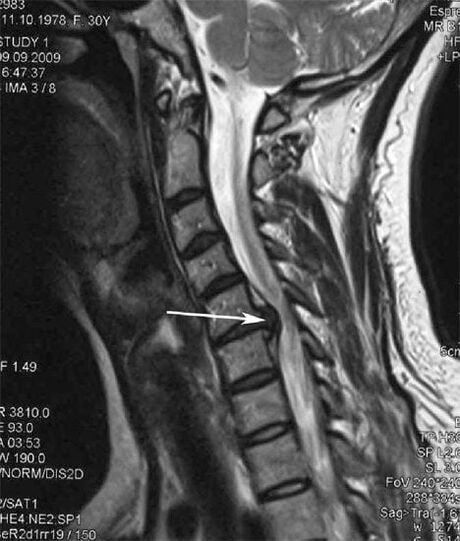

Im Anfangsstadium wird Osteochondrose mittels MRT erkannt.. Anschließend kann die Pathologie durch Röntgen diagnostiziert werden. Auf Röntgenaufnahmen der Halswirbelsäule werden eine Verringerung des Wirbelabstands, pathologische Veränderungen der Facettengelenke und Osteophytose festgestellt.

Viele Menschen klagen darüber, dass sie ihren Hals nicht drehen können, weil sie starke Schmerzen haben, wenn sie plötzlich etwas Schweres heben. Dieses Phänomen deutet auf die Entstehung eines Bandscheibenvorfalls hin. Die Ursache für Schmerzen im Rücken, Nacken und in den oberen Extremitäten ist das Einklemmen einer der aus dem Rückenmark austretenden Nervenwurzeln.

| Zervikale Osteochondrose | Das Auftreten pathologischer Veränderungen in einem oder mehreren Bewegungssegmenten der Wirbelsäule. Beeinträchtigung der Beweglichkeit der Wirbelsäule, Entwicklung myofaszialer Schmerzsyndrome und Einklemmen der Wirbelsäulenwurzeln. | Schmerzen, Parästhesien und motorische Veränderungen im Halsbereich, die sich bis zum Hals und den oberen Extremitäten erstrecken. Erkennung charakteristischer Veränderungen der Wirbelsäule mittels MRT und Röntgen (Osteophyten, verringerter Wirbelabstand, Anzeichen einer Schädigung der Zwischenwirbelgelenke) |